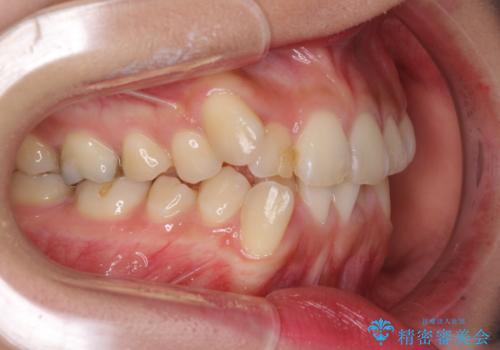

- 上下の八重歯を気にして来院された患者様です。

上下ともに八重歯の後ろの歯を1歯ずつ抜歯し、補助装置(リンガルアーチ)を用いて八重歯の位置を改善し、その後インビザラインにより矯正治療を行うこととしました。

途中海外留学をされたため、治療期間は長くなりましたが、事前に補助装置やワイヤー装置を併用したことで、きれいな歯列に仕上げることができました。